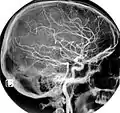

Magnetic Resonance Angiography

Normal carotidal arteriography